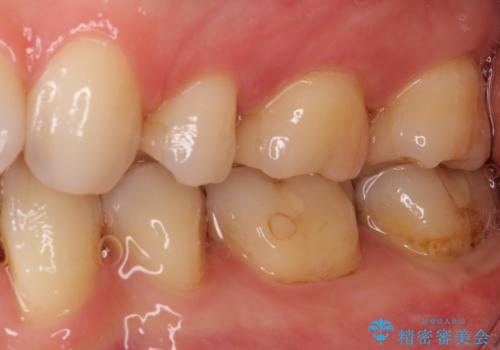

- 下の奥歯に虫歯ができてしまったとのことで来院された患者様です。

他にも気になる歯はありましたが、急を要する1歯のみをセラミックインレーにて修復治療を行うこととしました。

奥歯において、隣の歯と接触する部分に虫歯が及んでしまった場合、その場で充填を行う処置(コンポジットレジン修復)ですと、充填の縁に大きなギャップが生じてしまう可能性が高く、2次的な虫歯を引き起こすことになります。

また、処置した歯の後方にある歯は保険診療で使用するレジンインレーが装着されていますが、縁に虫歯が出来はじめていることが分かります。